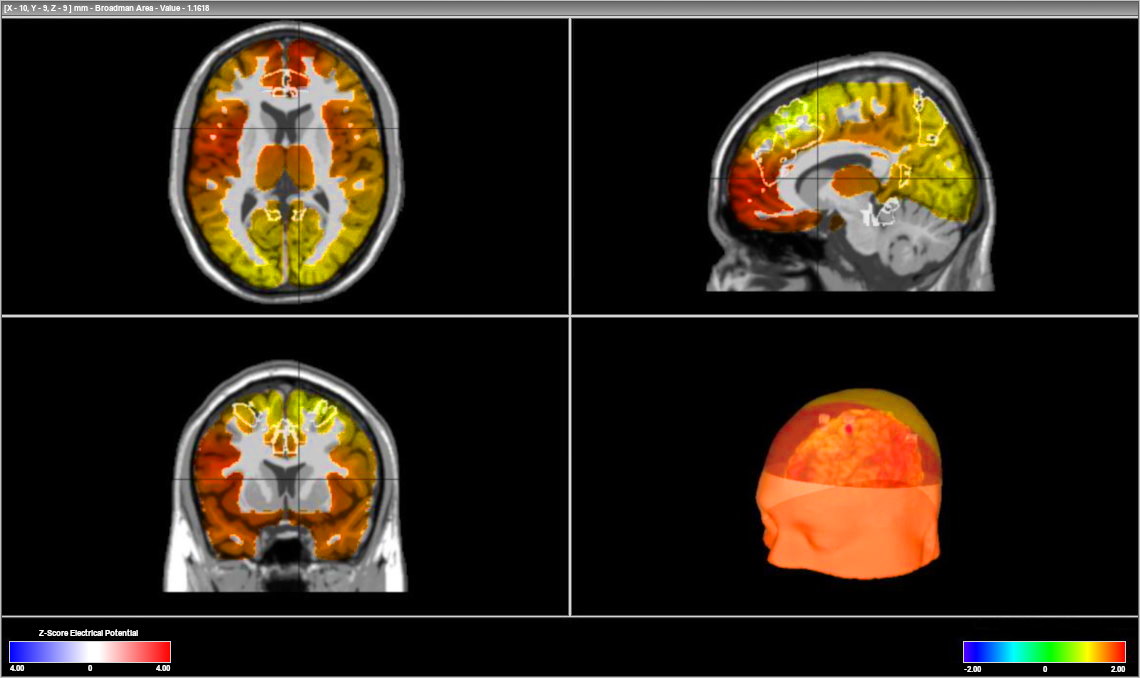

Brain Map

A 3 dimensional brain map image of brain activity levels at different frequencies.